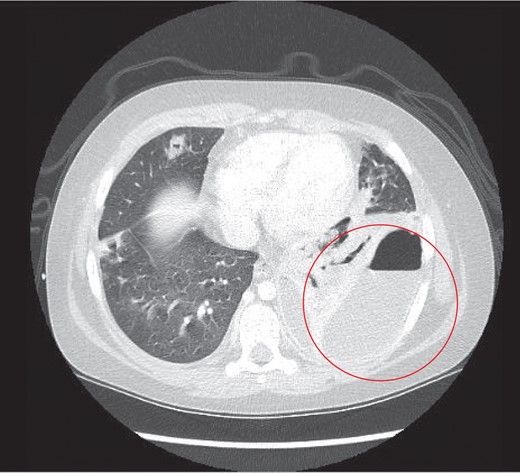

The child underwent a CT scan which demonstrated a large left sided empyema with an air fluid level (Fig. 2). The left lower lobe was collapsed with a multiloculated fluid collection. The appearances were suggestive of a necrotic lung abscess. The suggestion was that a Staphylococcus species was the most likely organism to account for the pattern of infection.

Thoracic CT study the next day, which revealed a large left sided lung empyema with an air fluid level. There was further consolidation and collapse within the left lower lobe and a multiloculated fluid collection.